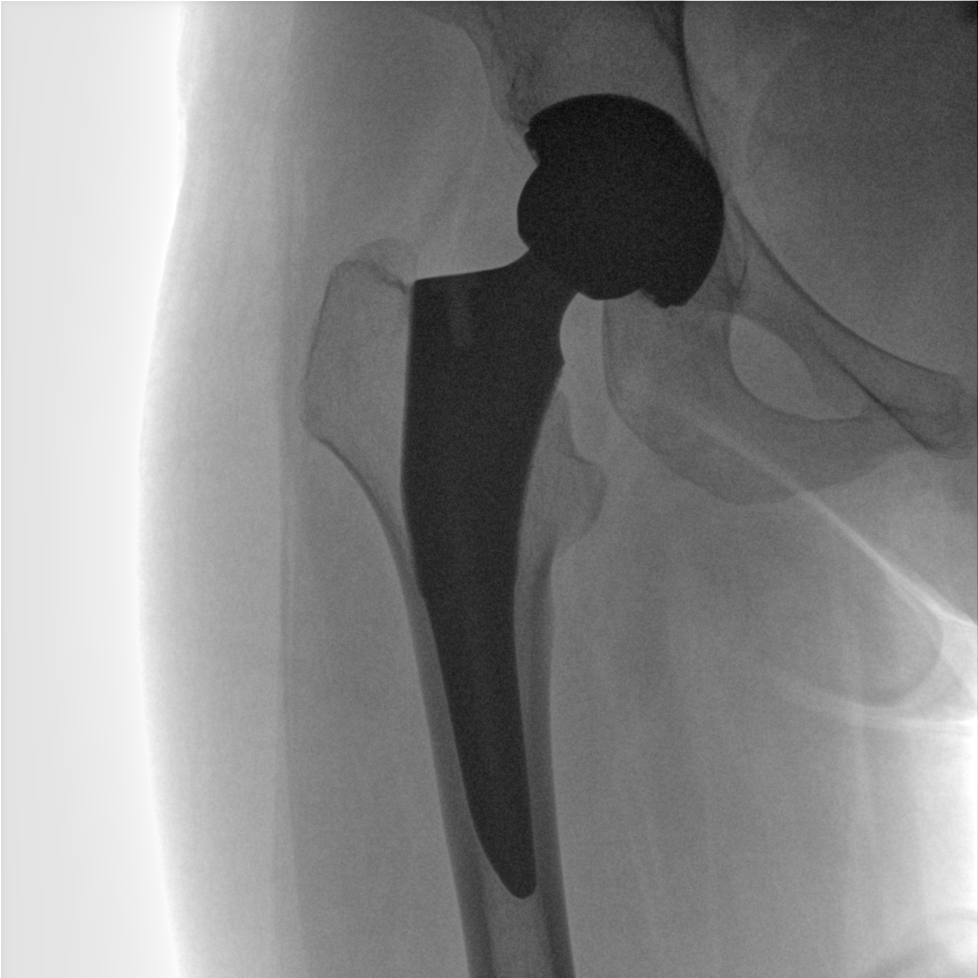

成像清晰、操作簡(jiǎn)易、擺位便捷,主要適用于骨科、脊柱外科、矯形外科、創(chuàng)傷骨科及手術(shù)室等,能大幅度提升手術(shù)水準(zhǔn),降低手術(shù)風(fēng)險(xiǎn)和并發(fā)癥的概率。

提供更大的術(shù)中三維成像視野,采集更多圖像信息,可一次拍全全段頸椎、全段腰椎、七節(jié)胸椎、雙側(cè)骶髂關(guān)節(jié)、股骨頭及單側(cè)盆骨。